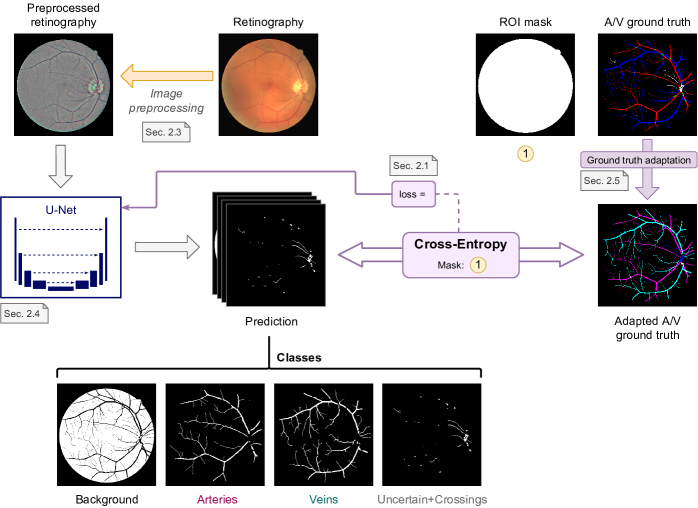

The traditional approach, depicted in Figure 2, addresses the SSCAV as a single multi-class semantic segmentation task.

Thus, for each pixel, an FCNN predicts the likelihoods of mutually exclusive classes. To that end, the network output is composed of channels that are tied with each other using a softmax activation. In this approach, Cross-Entropy (CE) is used as loss function, similarly to most state-of-the-art works in semantic segmentation. Formally, CE for joint vasculature segmentation and classification is defined as:

where denotes the network output for a given input retinography r and class , denotes its corresponding ground truth, denotes the weight of the class , denotes the number of classes and denotes a Region of Interest (ROI) mask, with the set of valid pixels in the image.

In this case, we consider classes, as depicted in Figure 2 (for this reason, we name this loss CE4). These classes correspond to “background”, “artery”, “vein”, and “uncertain or crossing”. Thus, as in [39], the fourth class includes both the vessels of uncertain class and the vessel crossings.

Following prior works [37, 38, 39], we set the weights for the “background”, “artery” and “vein” target classes to , so that all pixels of these classes count equally for the loss. Conversely, the weights for the “uncertain or crossing” class are set to . Thus, neither the vessel crossings, which simultaneously belong to the artery and vein classes, nor the uncertain pixels, provide learning feedback in this approach. This is the most commonly used approach in previous works [36, 37, 38, 40, 41].

Using this classification approach, it is possible to obtain the vascular segmentation map by performing a pixel-wise addition of the predicted probability maps for arteries, veins and “uncertain or crossings”, or using the inverse of the background class. However, it is not likely that the arterial and venular tree segmentation maps derived from the artery and vein classes are continuous, not even considering the “uncertain or crossings” class to complete them. The reason is that the network must decide to classify the vessel crossings as either of the above classes, in case of detecting them. Due to the fact that either the artery or the vein will be above the other, and the conditions for uncertain vessel classification are not commonly met at regular vessels, it is not probable that the “uncertain or crossings” class will be used. Thus the vascular tree for the vessel below will be discontinuous.